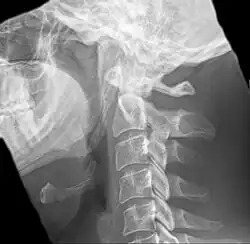

| Anteroposterior and lateral radiographs of cervical spine showing ossification of the stylohyoid ligament on both sides | |